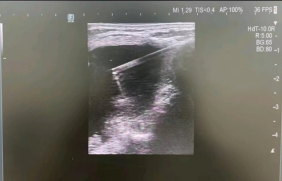

B超检查提示胡奶奶得的是

“甲状腺双叶结节”

肿瘤近10厘米大小,气管明显偏移

通过前期充分的术前准备

袁医生联合超声科主任邵军

在局麻下为胡奶奶实施了

甲状腺肿块微波消融术

术中按照术前既定的穿刺路线

麻醉针精准定位至结节病灶

3分钟后病灶成功被“热损毁”